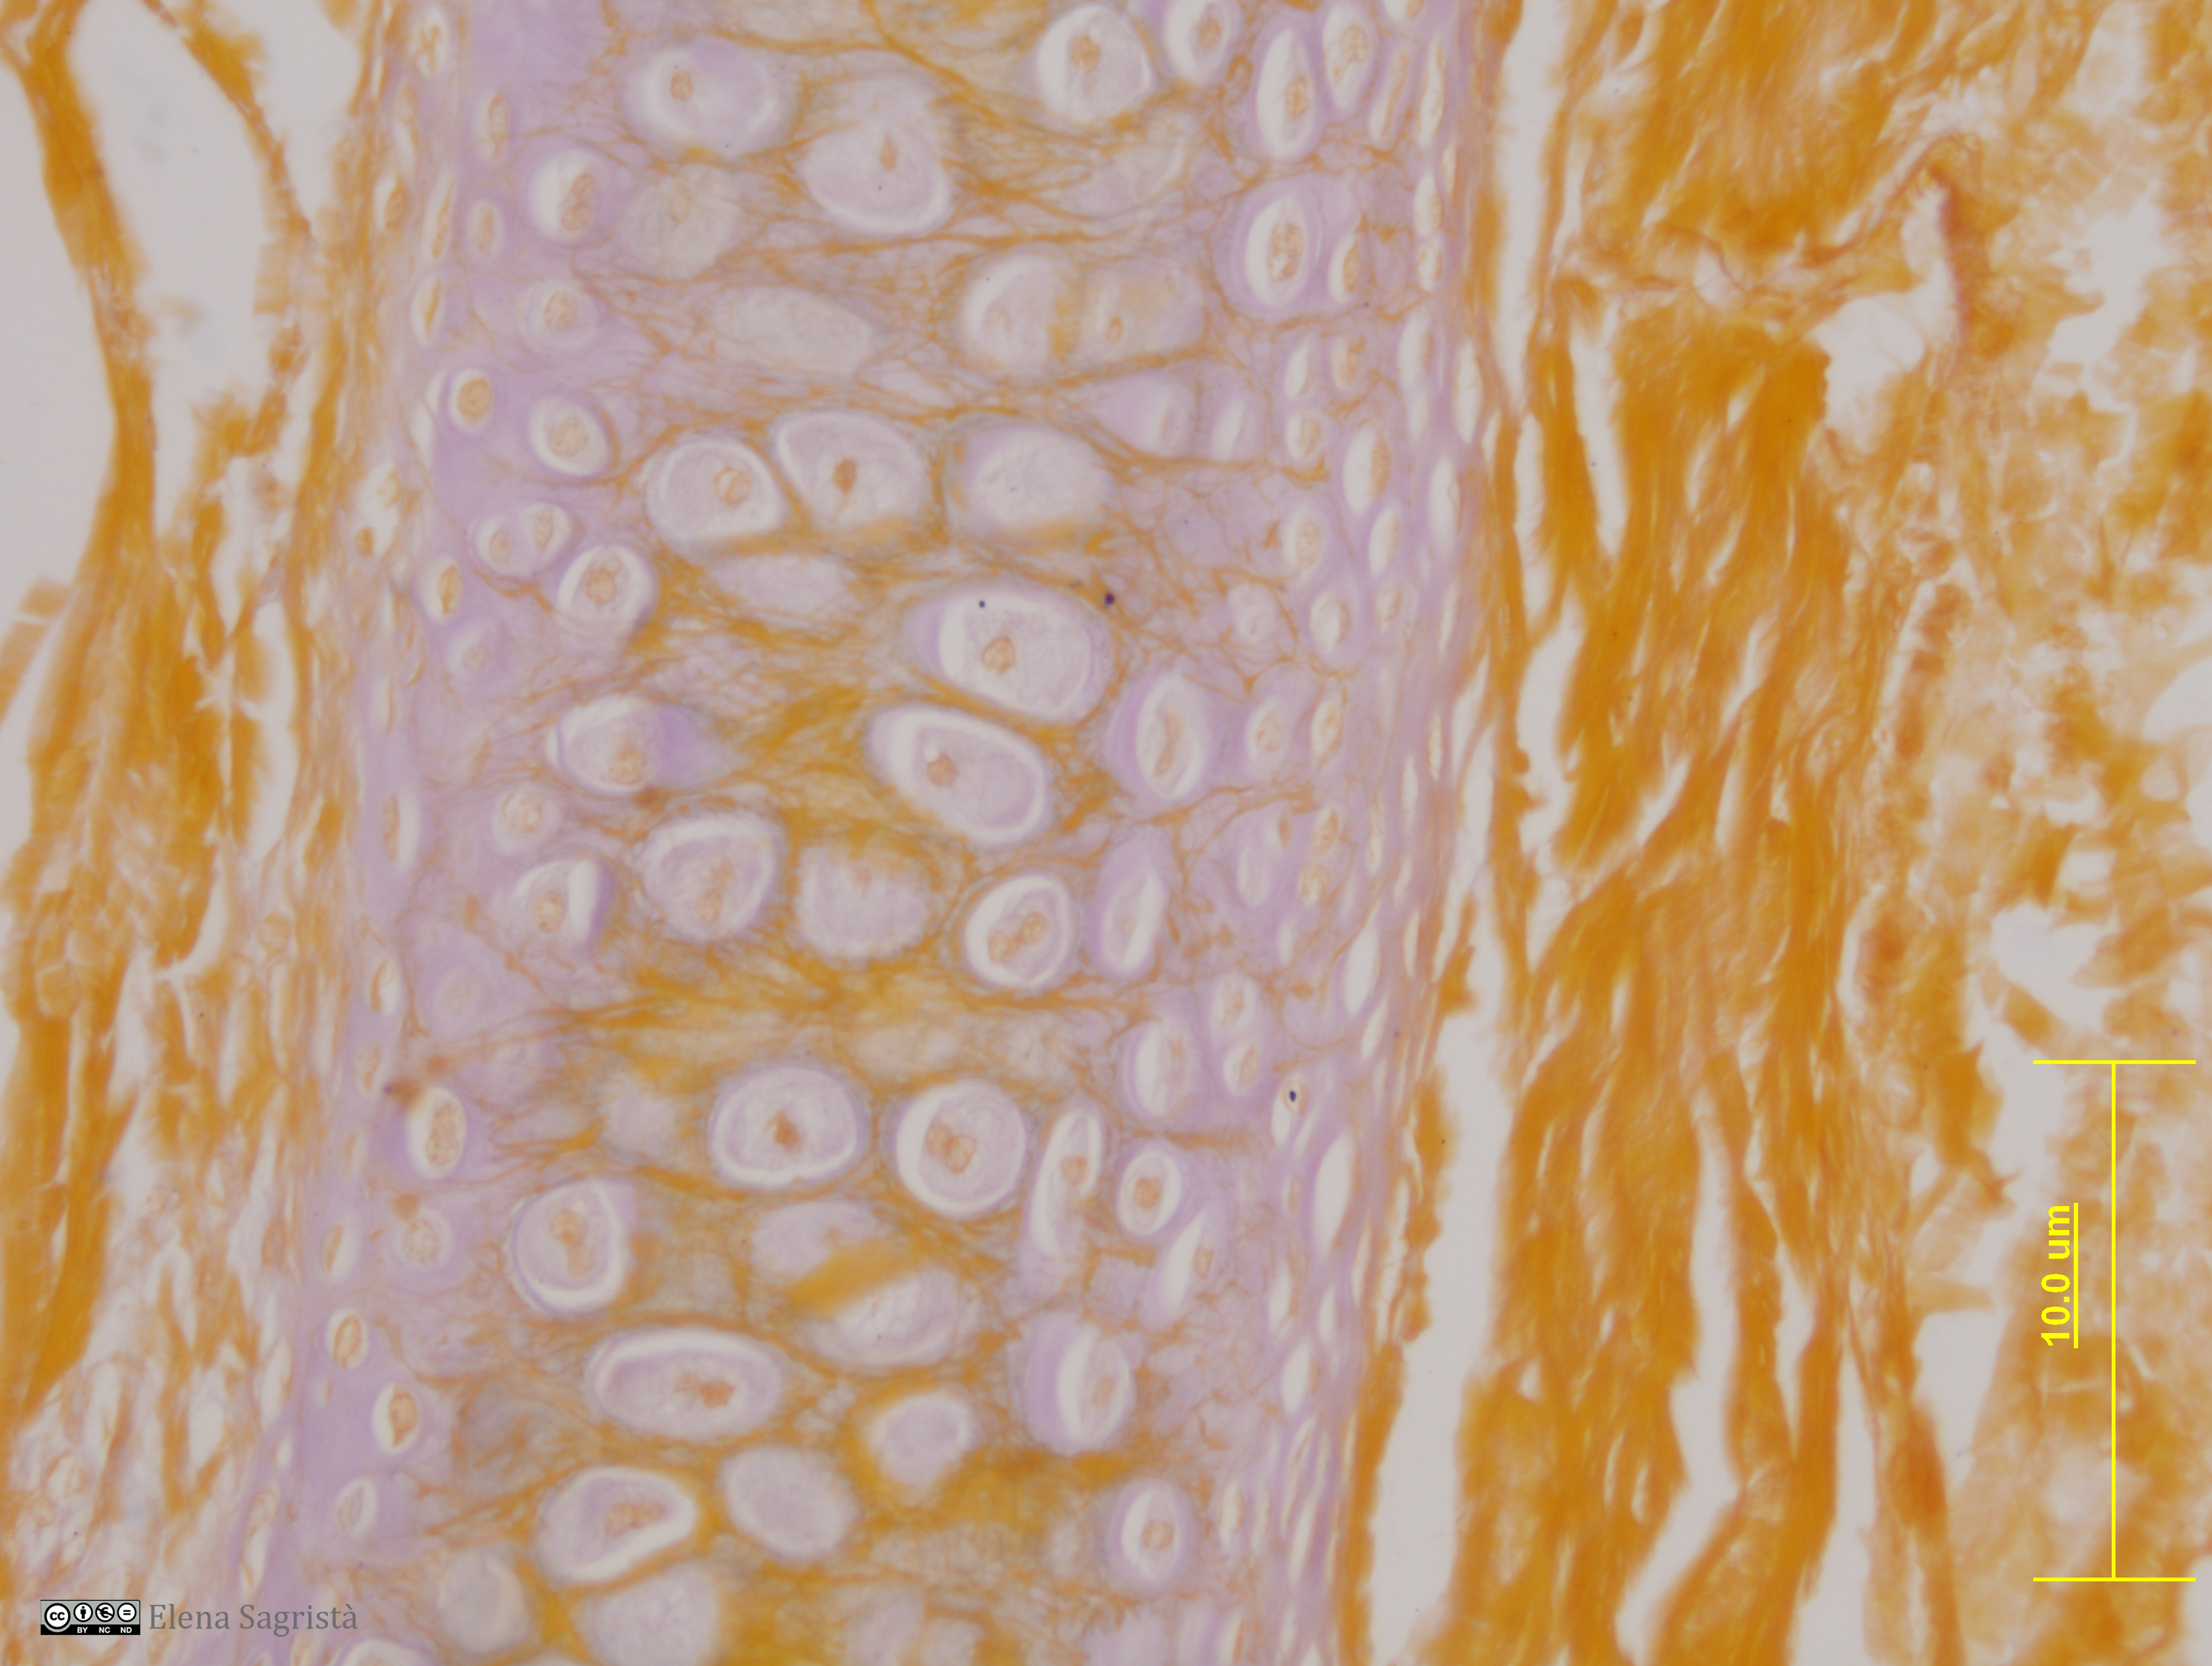

Histologia imatges: 04 Teixit cartilaginós

Imatges de preparacions histològiques de Teixit cartilaginós. Microscopia òptica.